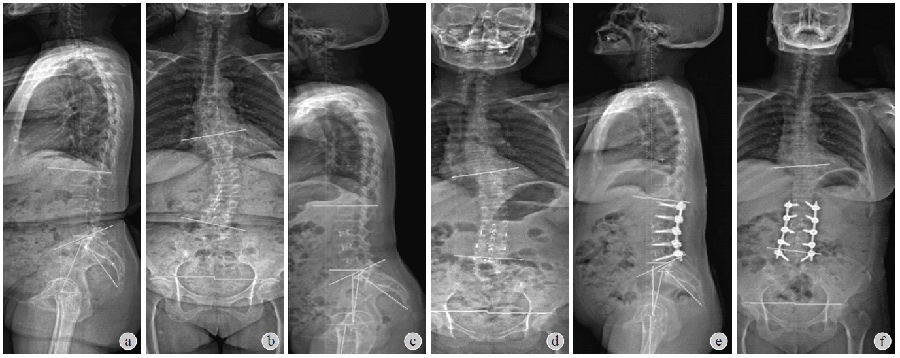

患者术前腰痛VAS评分平均为6.39±1.06,末次随访时VAS评分为3.37±1.05,较术前明显改善(t=15.02,P<0.001)。术前患者ODI平均为48.09±7.13,末次随访时平均为28.63±3.41,较术前明显改善(t=16.81,P<0.001)。典型病例见图1。

图1 患者女,65岁,退变性脊柱侧凸a、b:X线片示严重矢状面和冠状面失平衡,术前评估固定范围T10~L5;c、d:L2~5侧方植入OLIFcage后,X线片示无论是冠状面还是矢状面的平衡都得到明显改善,再次评估固定范围为L1~5;e、f:植入经皮椎弓根固定术后3年,X线片示冠状面和矢状面平衡维持良好